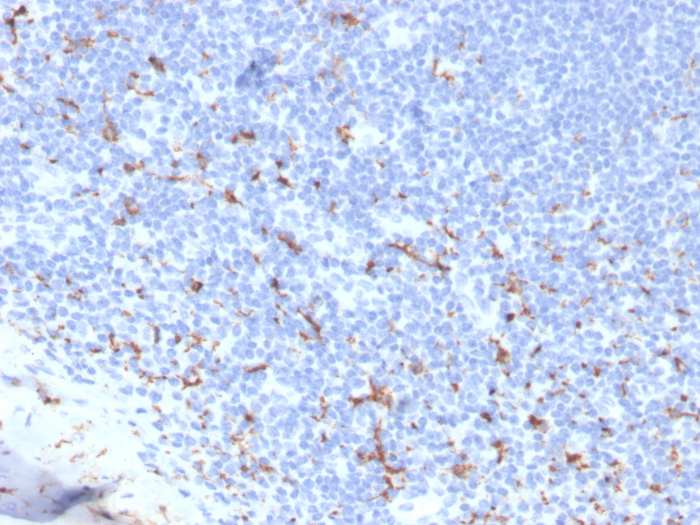

Formalin-fixed, paraffin-embedded human spleen stained with CD163 antibody (M130/3708R). HIER: Tris/EDTA, pH9.0, 45min. 2: HRP-polymer, 30min. DAB, 5min.